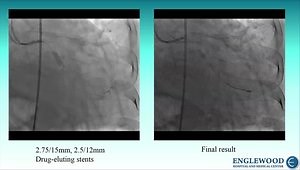

Angioplasty - Excimer Laser

Atherectomy - Excimer Laser